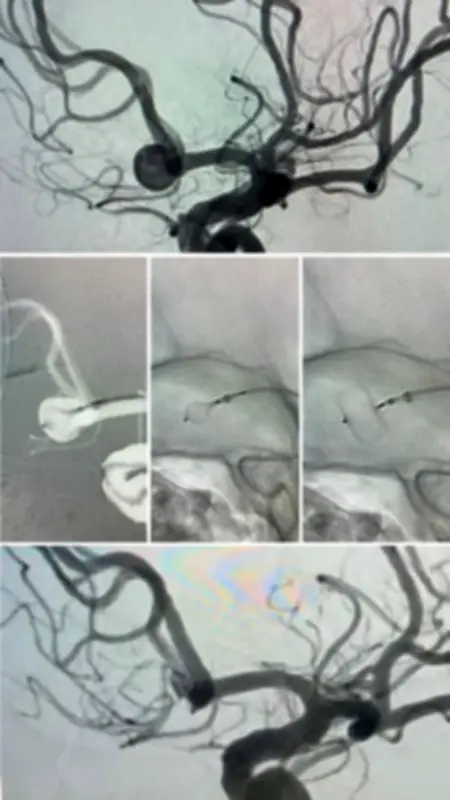

نجح فريق طبي متخصص في مستشفى المانع – فرع الدمام "عبدالله فؤاد" في علاج حالة طبية حرجة لمريض يبلغ من العمر 60 عامًا، كان يعاني من تمدد شرياني دماغي مصحوبًا بنزيف حاد في المخ. تم إجراء العملية باستخدام قسطرة دماغية دقيقة، إلى جانب تقنية طبية مبتكرة تُطبق لأول مرة في المستشفى، مما يمثل خطوة متقدمة في مجال الرعاية الصحية العصبية.

تعتمد التقنية الحديثة التي استخدمها الفريق الطبي على إغلاق التمدد الشرياني من داخل كيس التمدد نفسه، بواسطة جهاز طبي دقيق للغاية. هذا النهج الجديد يقدم عدة مزايا مهمة:

- يحد بشكل كبير من خطر تكرار النزيف الدماغي، مما يعزز سلامة المريض على المدى الطويل.

- يقلل الحاجة إلى استخدام الدعامات الطبية التقليدية ومميعات الدم، مما يخفض من المضاعفات المحتملة.

- يساهم في تسريع عملية التعافي وتحسين النتائج السريرية للمرضى الذين يعانون من حالات عصبية حرجة.